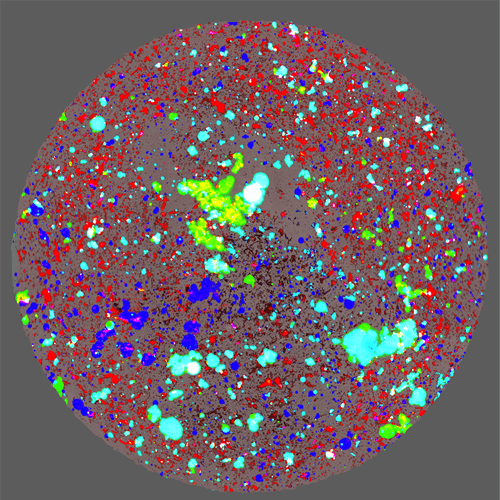

3、明確確認檢測到的SVP為聚集衣殼

上面研究的三種血清型中穩定的AAV2樣品在不同條件下受到壓力,并結合使用明場(BMI)和熒光(熒光膜顯微鏡– FMM)進行分析。樣品用硫黃素T(ThT)染色,這是一種熒光染料,可以與聚集的蛋白質特異性結合,但不能與非蛋白質顆粒結合,后者可以源自塑料,橡膠或降解的添加劑。

熱應激AAV2樣品中的衣殼聚集

在來自Aura的組合明場(非蛋白質,藍色)和熒光(蛋白質,紅色)圖像中,觀察到熱應激AAV2樣品中衣殼高度聚集。